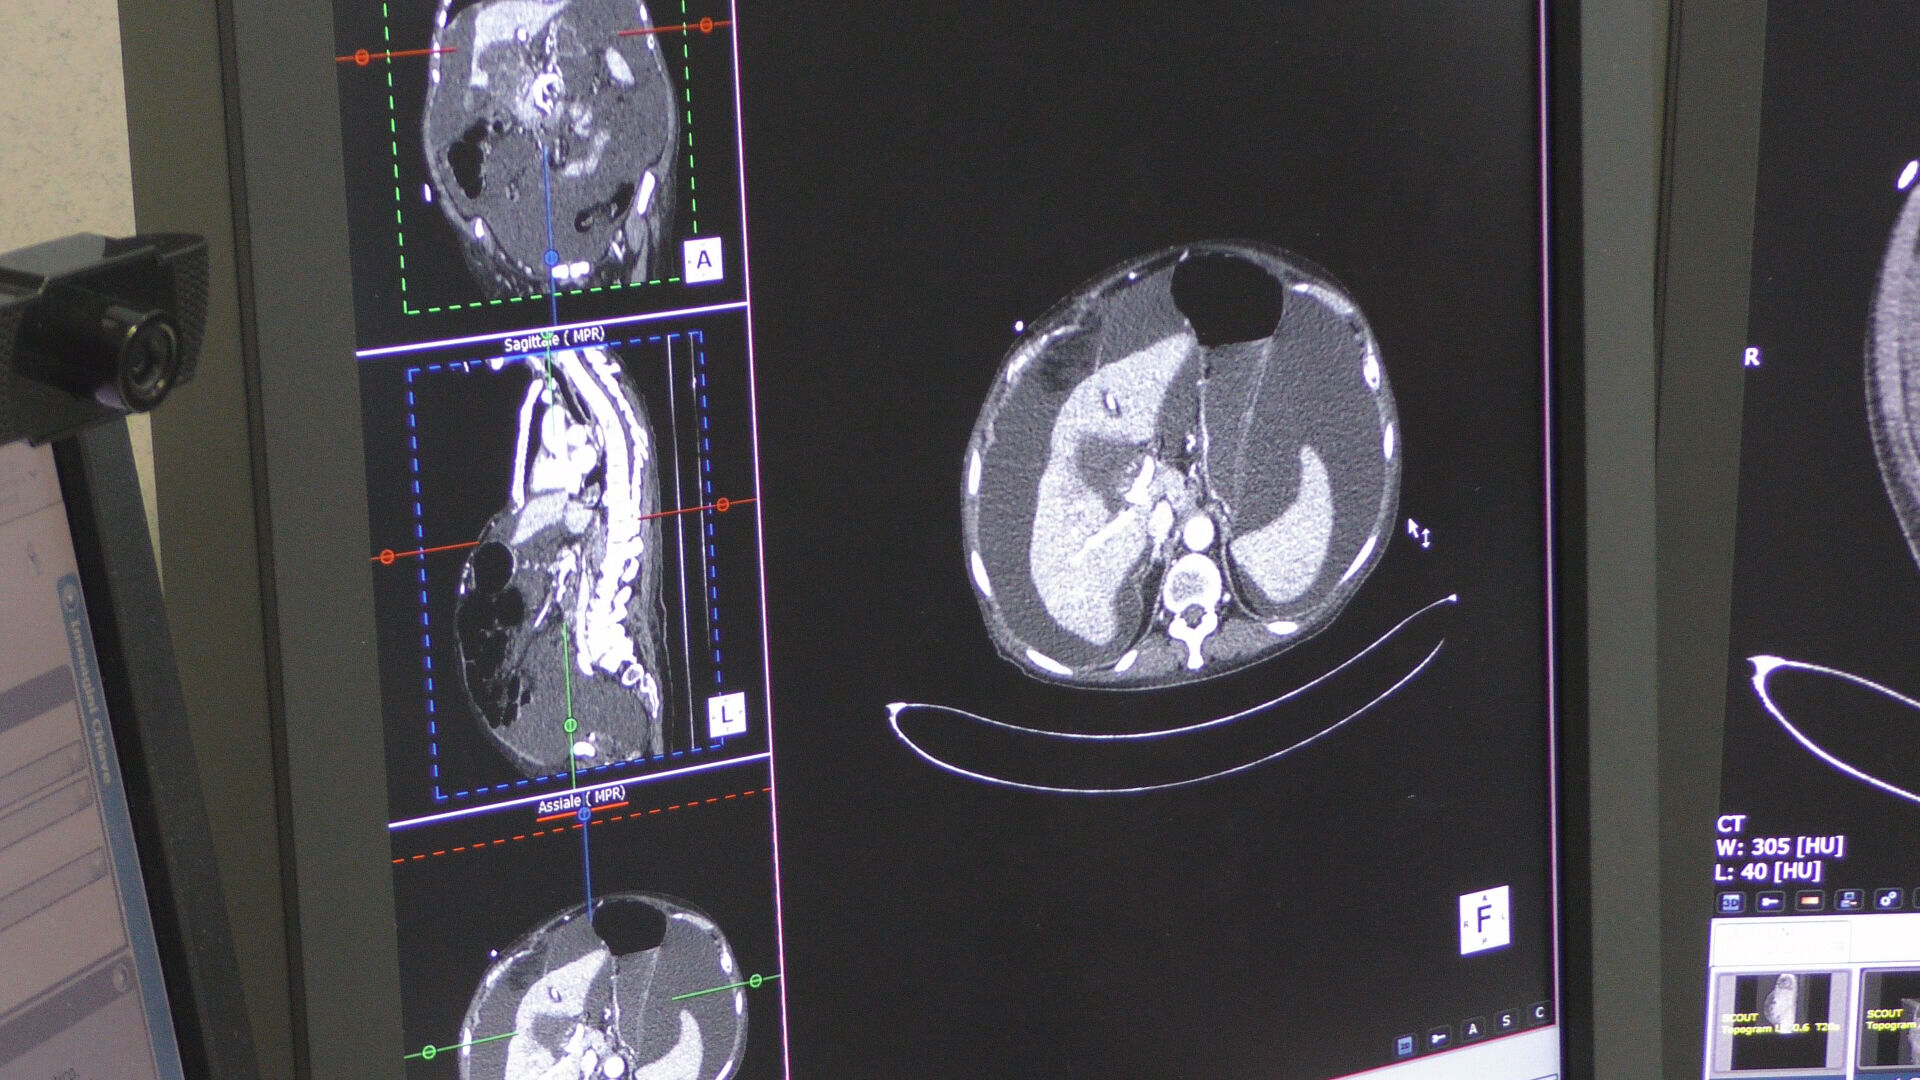

L’Azienda di rilievo nazionale e alta specializzazione (Arnas) ‘G. Brotzu’ ha azzerato la lista d’attesa per le Tac programmate nei follow-up dei pazienti assistiti nei reparti di Oncoematologia e Oncologia medica dell’ospedale Businco. Un traguardo reso possibile dal piano d’abbattimento avviato il 16 dicembre, che ha portato, in circa 40 giorni, all’esecuzione di 215 Tac ‘total body’, per un equivalente complessivo di oltre mille segmenti Tac effettuati per attività di controllo.

Il piano messo in campo ha consentito di incidere radicalmente su una lista che da circa tre anni pesava sui tempi d’attesa dei follow-up, attraverso la riorganizzazione e rimodulazione delle risorse, prestazioni svolte anche nei giorni prefestivi e il supporto della Tac dell’ospedale A. Cao (Microcitemico), resa accessibile ai pazienti oncologici attraverso percorsi dedicati, in totale sicurezza.

In totale sono circa 100mila le prestazioni di radiologia diagnostica che ogni anno vengono eseguite nelle strutture sanitarie dell’Arnas. “A febbraio – fa sapere l’assessore – l’azienda ad alta specializzazione avvierà un nuovo programma che punterà all’azzeramento delle liste per gli esami del comparto diagnostico della senologia, con l’esecuzione di 900 prestazioni, tra mammografie ed ecografie mammarie nell’arco di quattro/sei settimane. Esami indispensabile per la prevenzione e la diagnosi precoce dei tumori”